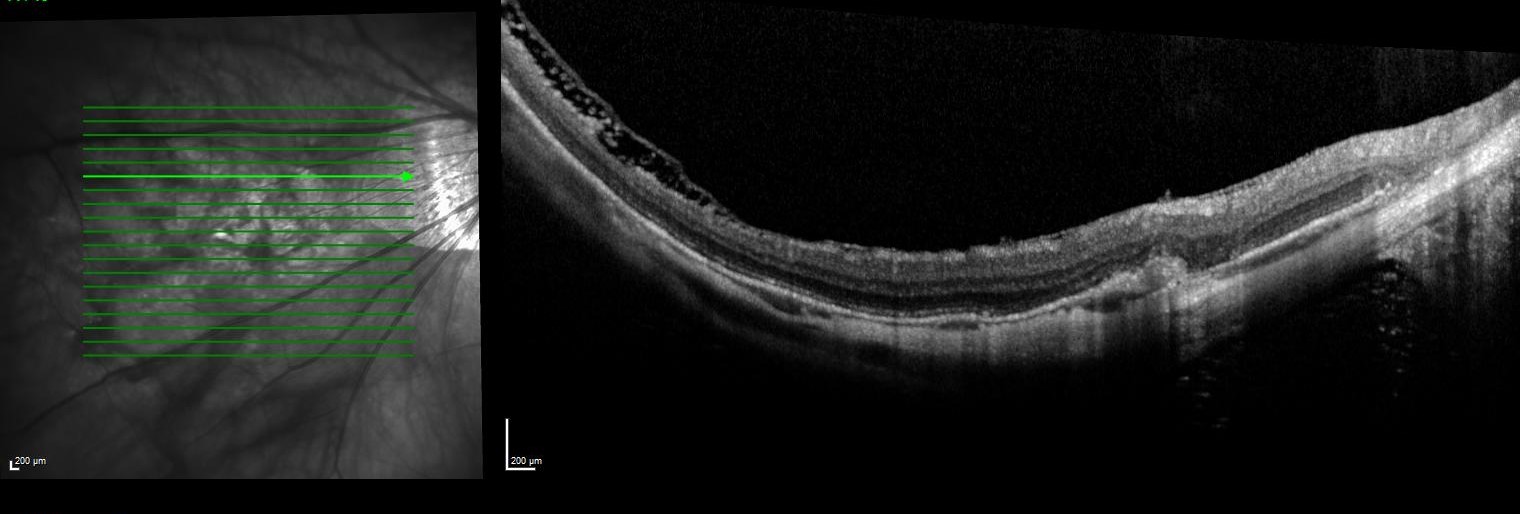

Trial-fitting with the Eyespace Scleral lens was carried out with the aid of anterior OCT to assess central clearance and landing zone alignment. Despite his large corneal diameter (HVID) the lens size of 16.5mm was chosen as the larger 17.5mm size decentered inferiorly following insertion. This also matched the size of the KATT lens he has used in the past. I always assess flexure of the lens with over-topography during trial fitting as this gives me an idea of the level of scleral toricity. The Scleral Shape Study from Pacific University showed us that the majority of sclera are asymmetrical and tend to be flatter in the nasal aspect. Fitting a spherical scleral lens to an asymmetrical sclera often results in lens flexure, leading to residual astigmatism. In moderate-severe cases it can also cause the lens to be unstable on the eye.

Anterior OCT of the lens showing 160µm of central clearance and well-aligned base curve

OCT of the inferior scleral landing zone showing limbal clearance and well-aligned landing angle

Using the data from the trial fitting process the patient’s first custom lens was designed with 200µm of sagittal difference between meridians and a spherical base curve and power of 7.8mm and -3.50D respectively. On delivery the lens had even scleral alignment and after settling 160µm of central clearance. The lens was quick to align with the ‘flat’ meridian’s marking along 30 degrees, matching the principal meridians of flexure on the over-topography of the trial lens.